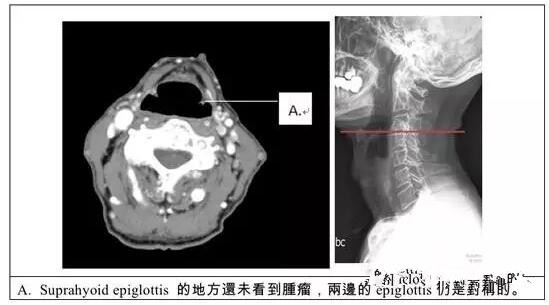

4.CT及MRI检查

CT能很好地显示肿瘤侵犯的程度及范围,并能发现临床上难发现的早期颈淋巴结转移。MRI通过三维成像,可立体的了解肿瘤侵犯的范围,区分肿瘤与其他软组织影,了解肿瘤与周围血管的关系,以及有无颈淋巴结转移等。